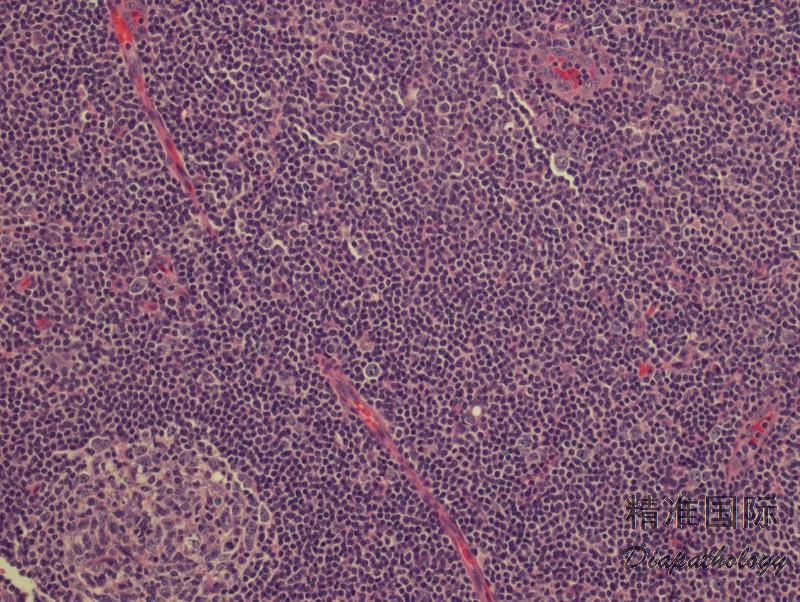

淋巴细胞丰富型经典型霍奇金淋巴瘤

Lymphocyte-Rich Classical Hodgkin Lymphoma, LRCHL

霍奇金淋巴瘤(Hodgkin lymphoma, HL)是一种来源于单克隆 B 细胞的肿瘤,分为结节性淋巴细胞为主型霍奇金淋巴瘤(nodular lymphocyte predominant Hodgkin lymphoma, NLPHL)和经典型霍奇金淋巴瘤(classical Hodgkin lymphoma, CHL)。后者又分为四种组织学亚型:结节硬化型经典霍奇金淋巴瘤(NSCHL)、淋巴细胞丰富型经典霍奇金淋巴瘤(LRCHL)、混合细胞型经典霍奇金淋巴瘤(MCCHL)、淋巴细胞消减型经典霍奇金淋巴瘤(LDCHL)。 CHL 的组织学共同特征是少量的 Hodgkin 细胞(单核)或 Reed-Sternberg 细胞(多核)散在分布于大量的反应性背景细胞中,它们包括淋巴细胞、嗜酸细胞、粒细胞、浆细胞和组织细胞及不等量胶原纤维。 LRCHL 亚型组织学表现为少量 HRS 细胞散在分布于呈结节状或偶尔弥漫生长的小淋巴细胞背景中,无粒细胞和嗜酸细胞,无纤维化。

少见的亚型,发病年龄较其它亚型大,男性多见。常见为外周淋巴结,纵隔很少受累。

有两种生长模式:结节型和弥漫型。绝大多数病例呈结节型生长,结节为扩大的套区,有时可见偏心的生发中心。典型的 HRS 细胞散在分布结节中,有时肿瘤细胞类 LP 细胞。粒细胞和嗜酸细胞罕见(结节之间)或缺如。无纤维化。少数病例背景淋巴细胞呈现弥漫生长模式,常混有组织细胞。